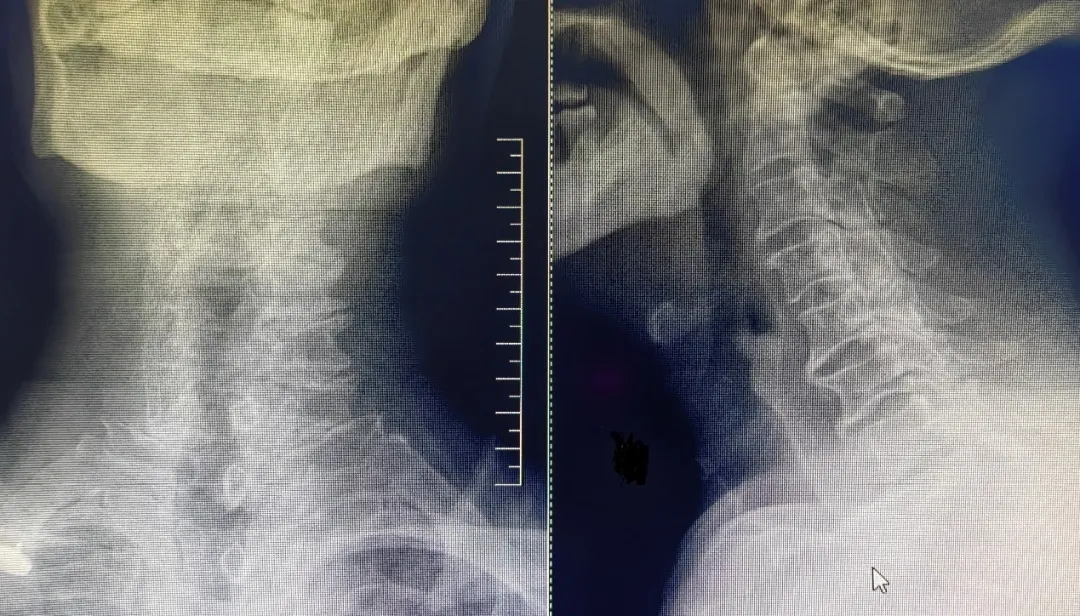

患者,男性,左上肢内侧疼痛剧烈,保守治疗无效,就诊于我院脊柱外科中心B区,诊断为神经根型颈椎病,C7/T1节段,左侧神经根管骨质增生严重,颈前路手术因胸骨阻挡难以实施,后路手术减压风险高、担心减压不彻底且创伤大。赵文奎博士了解患者病情后,用北医三院的诊疗理念,从影像学资料研判、诊断与鉴别诊断、治疗方案的制定等不同方面进行了详细分析,与我院脊柱外科中心B区医疗团队共同为患者制定了“精准化”手术方案——经皮内镜颈椎椎板切除神经根管减压术。